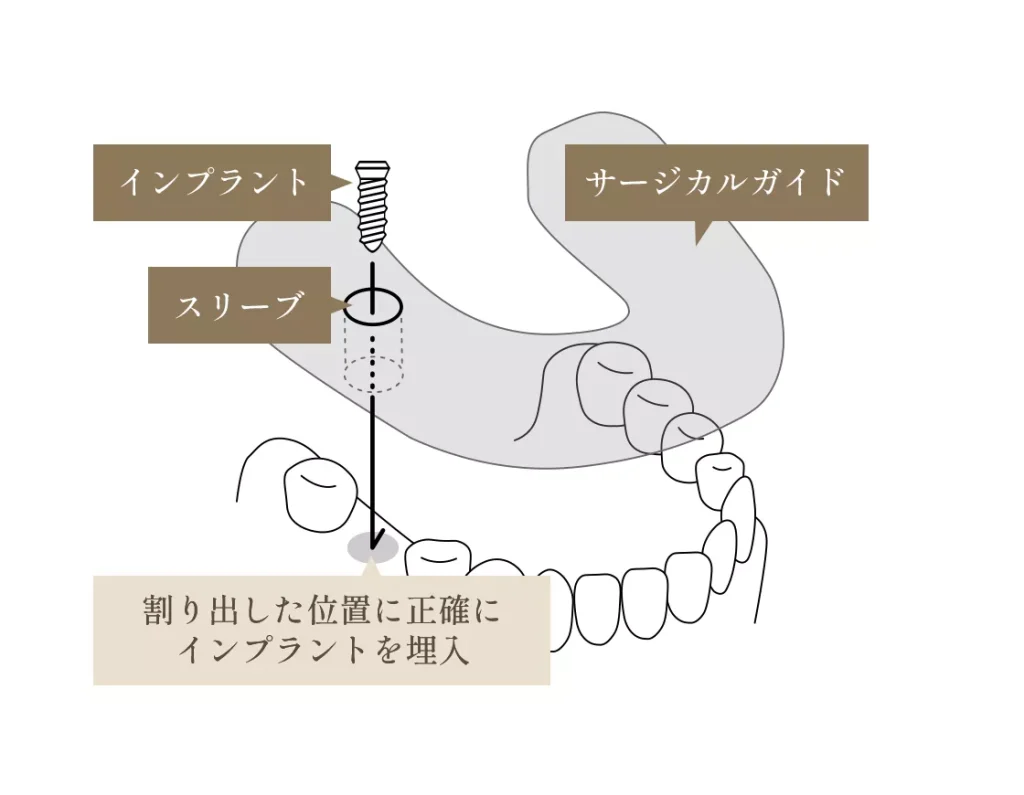

安全かつ正確な手術を実現する「サージカルガイド」

当院では、コンピューターによる精密なシミュレーションと連動した「サージカルガイド」を使用することで、安全で正確な手術を行っています。これにより、歯茎の切開を最小限に抑える「低侵襲なインプラント治療」が可能になります。

サージカルガイドとは?

サージカルガイドとは、インプラントを埋め込むためのオーダーメイドの「手術用テンプレート」です。事前に撮影したCTデータを用いてコンピューター上で緻密なシミュレーションを行い、インプラントを埋入する最適な位置、深さ、角度を正確に設定して作製します。

コンピュータ上で、骨の量や形、神経・血管の位置を正確に把握し、インプラントがどのように入るかをシミュレーションします。

さらに、最終的な被せ物(上部構造)のことも考慮し、他の歯との噛み合わせや審美性のバランスをシミュレーションすることで、機能的にも見た目にも美しい仕上がりを目指します。

サージカルガイドを活用するメリット

- 低侵襲な手術: 歯茎の切開を最小限に抑えられるため、出血や術後の腫れ、痛みが大幅に軽減されます。

- 安全性の向上: 骨、血管、神経を損傷するリスクを低減します。

- 手術時間の短縮: 事前計画に基づき、効率的な手術が可能になります。

- 精密な仕上がり: 計画通りの正確な位置にインプラントを埋入できるため、審美性や機能性に優れた治療結果が得られます。

治療の流れ

- 精密検査: 3DでのCT撮影を行い、顎の骨や神経、血管の位置などを詳細に確認します。

- シミュレーション: 取得したデータを基に、コンピューター上でインプラントの最適な埋入位置をシミュレーションします。

- ガイド作製: シミュレーション結果に基づいて、正確な位置にインプラントを埋入するためのサージカルガイドを作製します。

- 手術: ガイドを装着した状態で手術を行うため、歯茎の切開を最小限に抑え、計画通りにインプラントを埋入します。